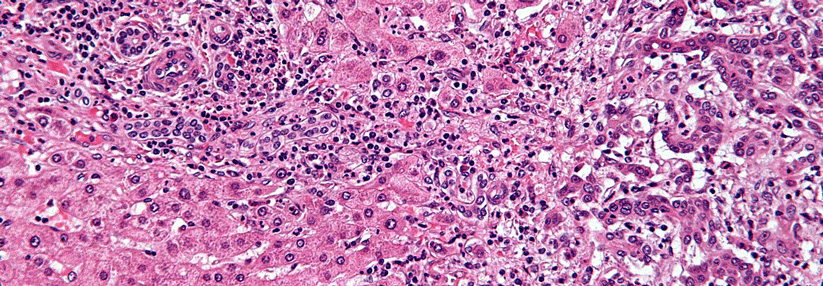

Gallengangskarzinome machen 1,7 % aller malignen Tumoren aus und sind damit eine seltene Entität. Gallengangskarzinome machen 1,7 % aller malignen Tumoren aus und sind damit eine seltene Entität. © iStock / wildpixel